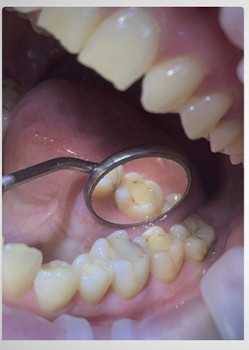

- Эстетическая реставрация зубов композитным материалом.